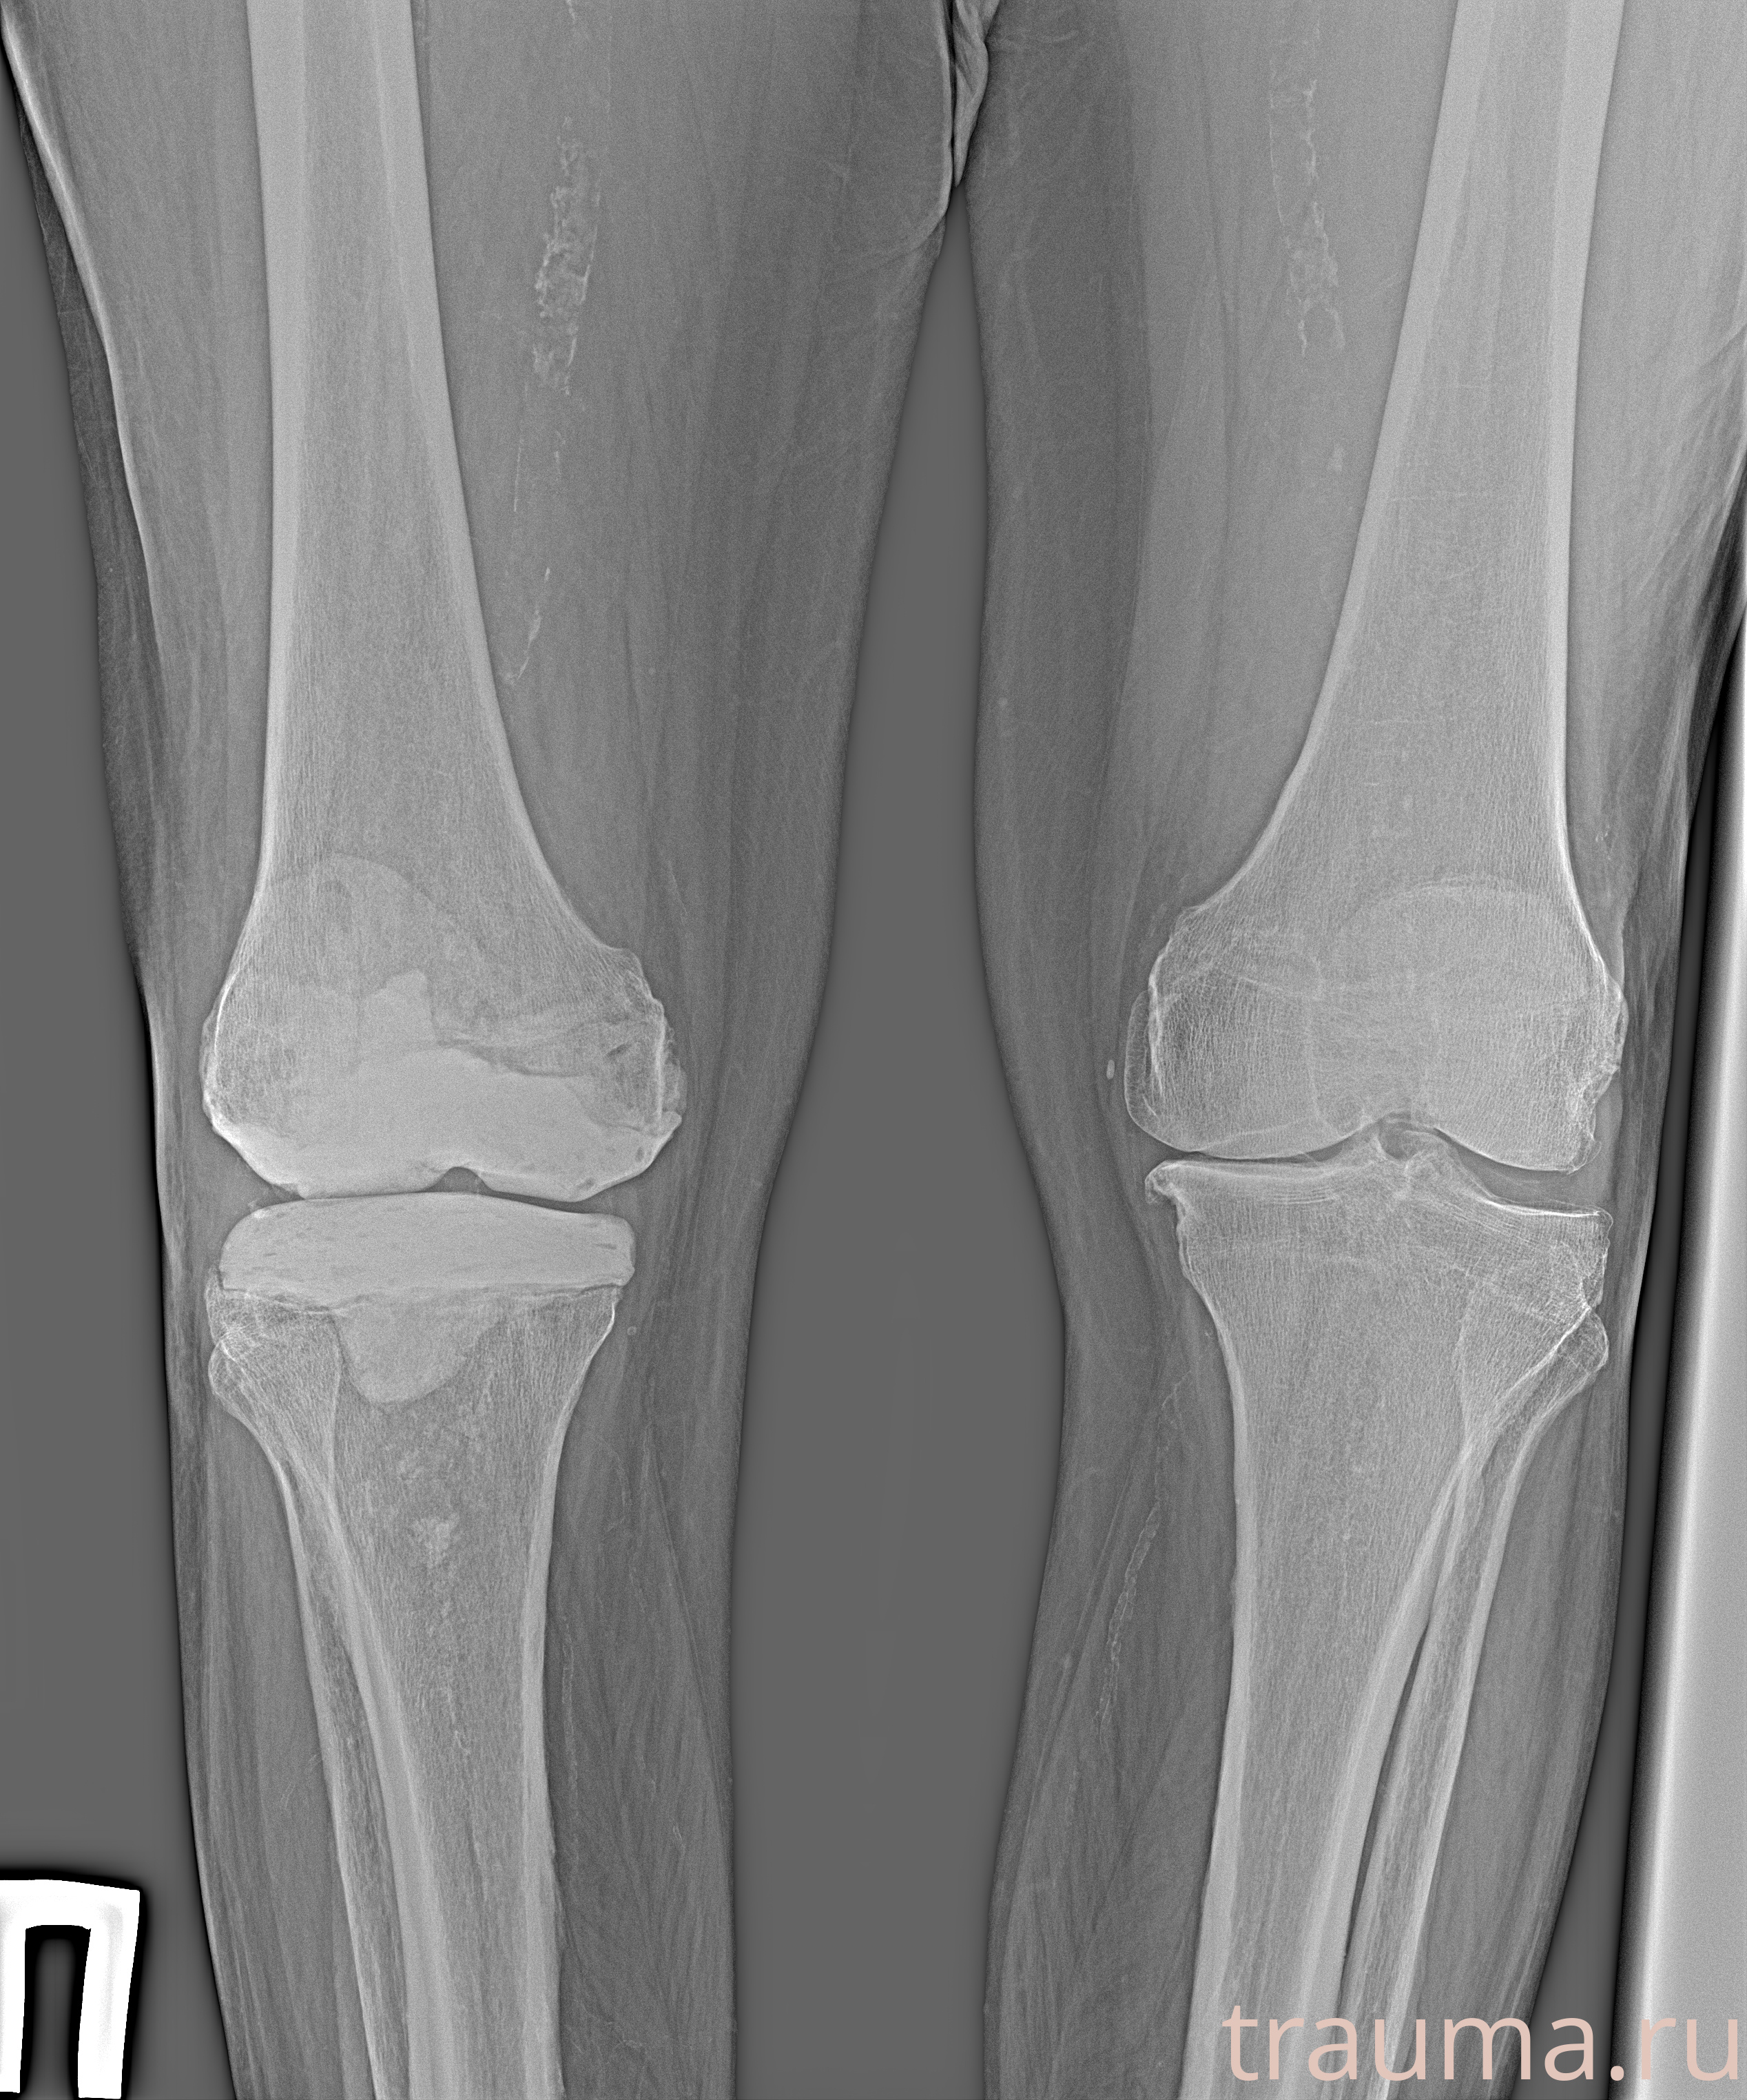

Рентген на дому: по вашему адресу приезжает врач-рентгенолог, травматолог-ортопед с мобильным рентгеновским аппаратом, проводит диагностику травмы или заболевания, делает необходимые рентгенограммы, дает рекомендации по дальнейшему лечению. Получить качественные снимки в домашних условиях возможно благодаря уникальной методике, разработанной МосРентген Центром для института  Склифосовского